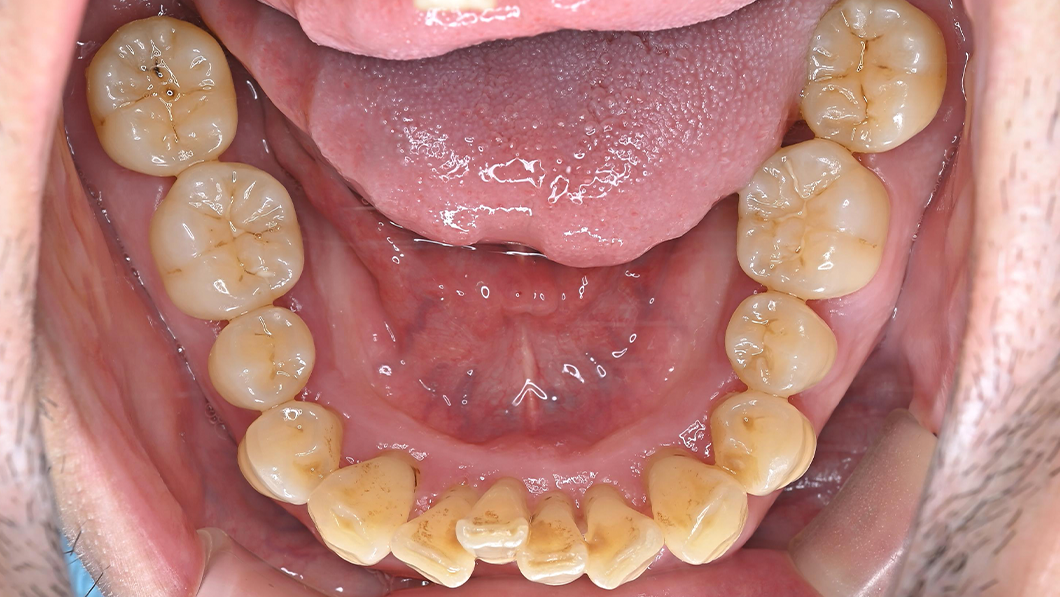

【40代 男性】歯周基本治療

治療前

主訴 全額的歯周病による歯周組織の炎症

期間 2-3ヶ月程度

1-2週間に1回

費用 保険診療内

治療内容 SC、SRP、歯科衛生士実地指導、TCH指導